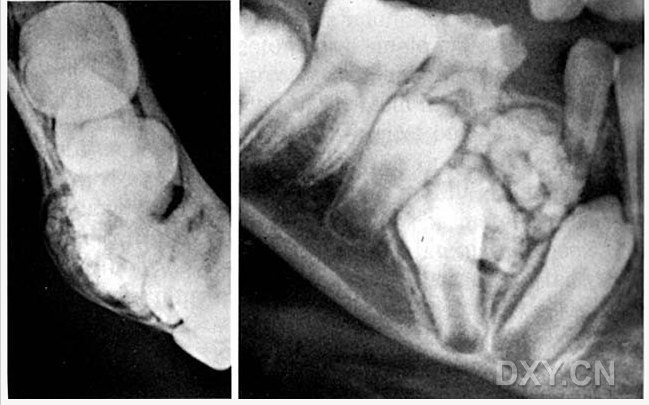

球狀上頜囊腫

含牙囊腫

球狀上頜囊腫    含牙囊腫